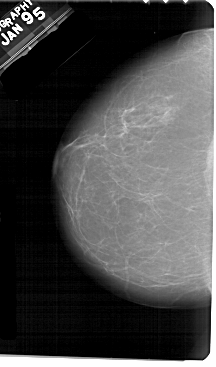

A_1943_1.RIGHT_MLO

RIGHT_MLO LINES 5491 PIXELS_PER_LINE 3121 BITS_PER_PIXEL 12 RESOLUTION 43.5 OVERLAY